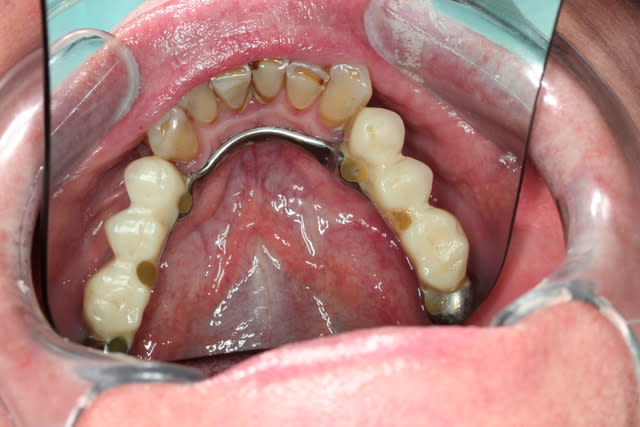

Allez trois autre photos

Ne me dites que les dents restantes à la mandibule sont pourries sur le plan paro... Je le sais

Prochainement étape : virer les molaires avec PRFs et poser déjà deux implants en 35 45 en enfoui...et qd les PRFs auront fait leur oeuvre : implanto totale du bas